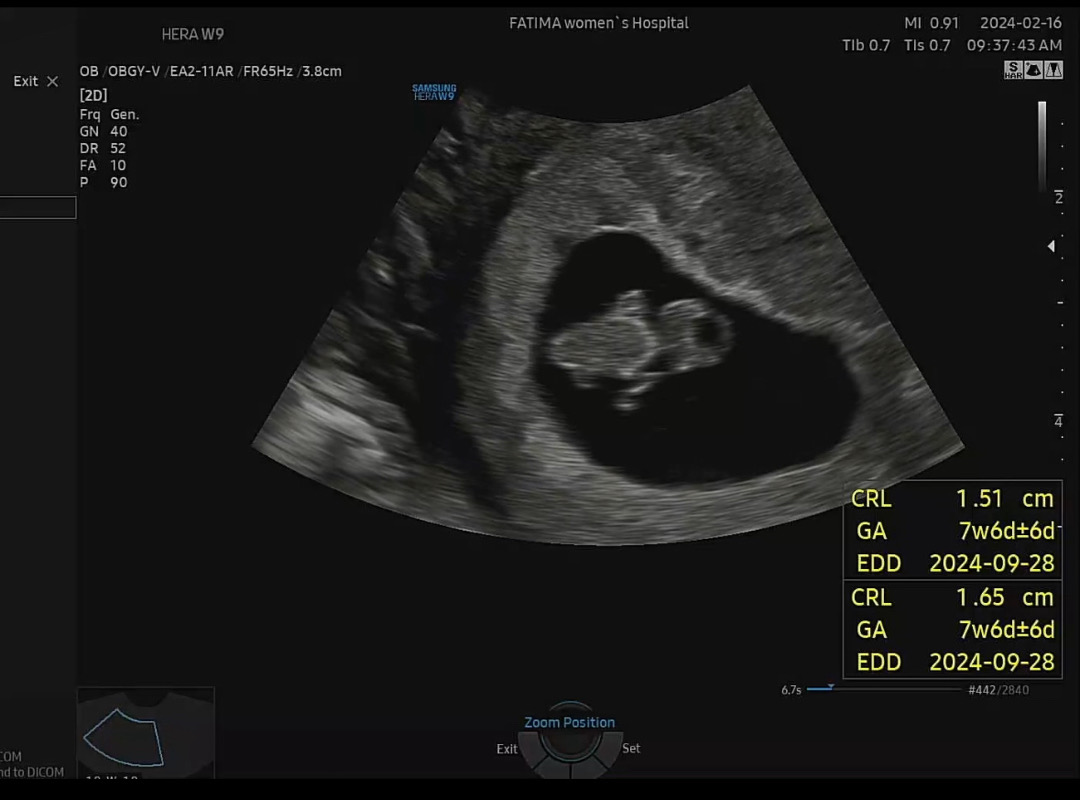

7주5일차 초음파 요게 젤리곰일까요?🐻

콕콕하던배가 생리통처럼 아리게 아파서 엄청 걱정하다가 검진날이라 오늘 다녀왔는데 심장소리도 듣고왔네요ㅠ.ㅠ 초반에 살짝 출혈도 있어서 걱정이엄청 많았는데 이번주는 유독 생리통처럼 배가 너무 아프더라구요 ㅠ.ㅠ 잘크고있단 신호였나봐요 😂 오늘 드디어 2등신을 처음봤는데 요 모습이 젤리곰이 맞을까요??🐻 3주뒤에 오라는데 벌써 애가 타네요!!ㅋㅋ